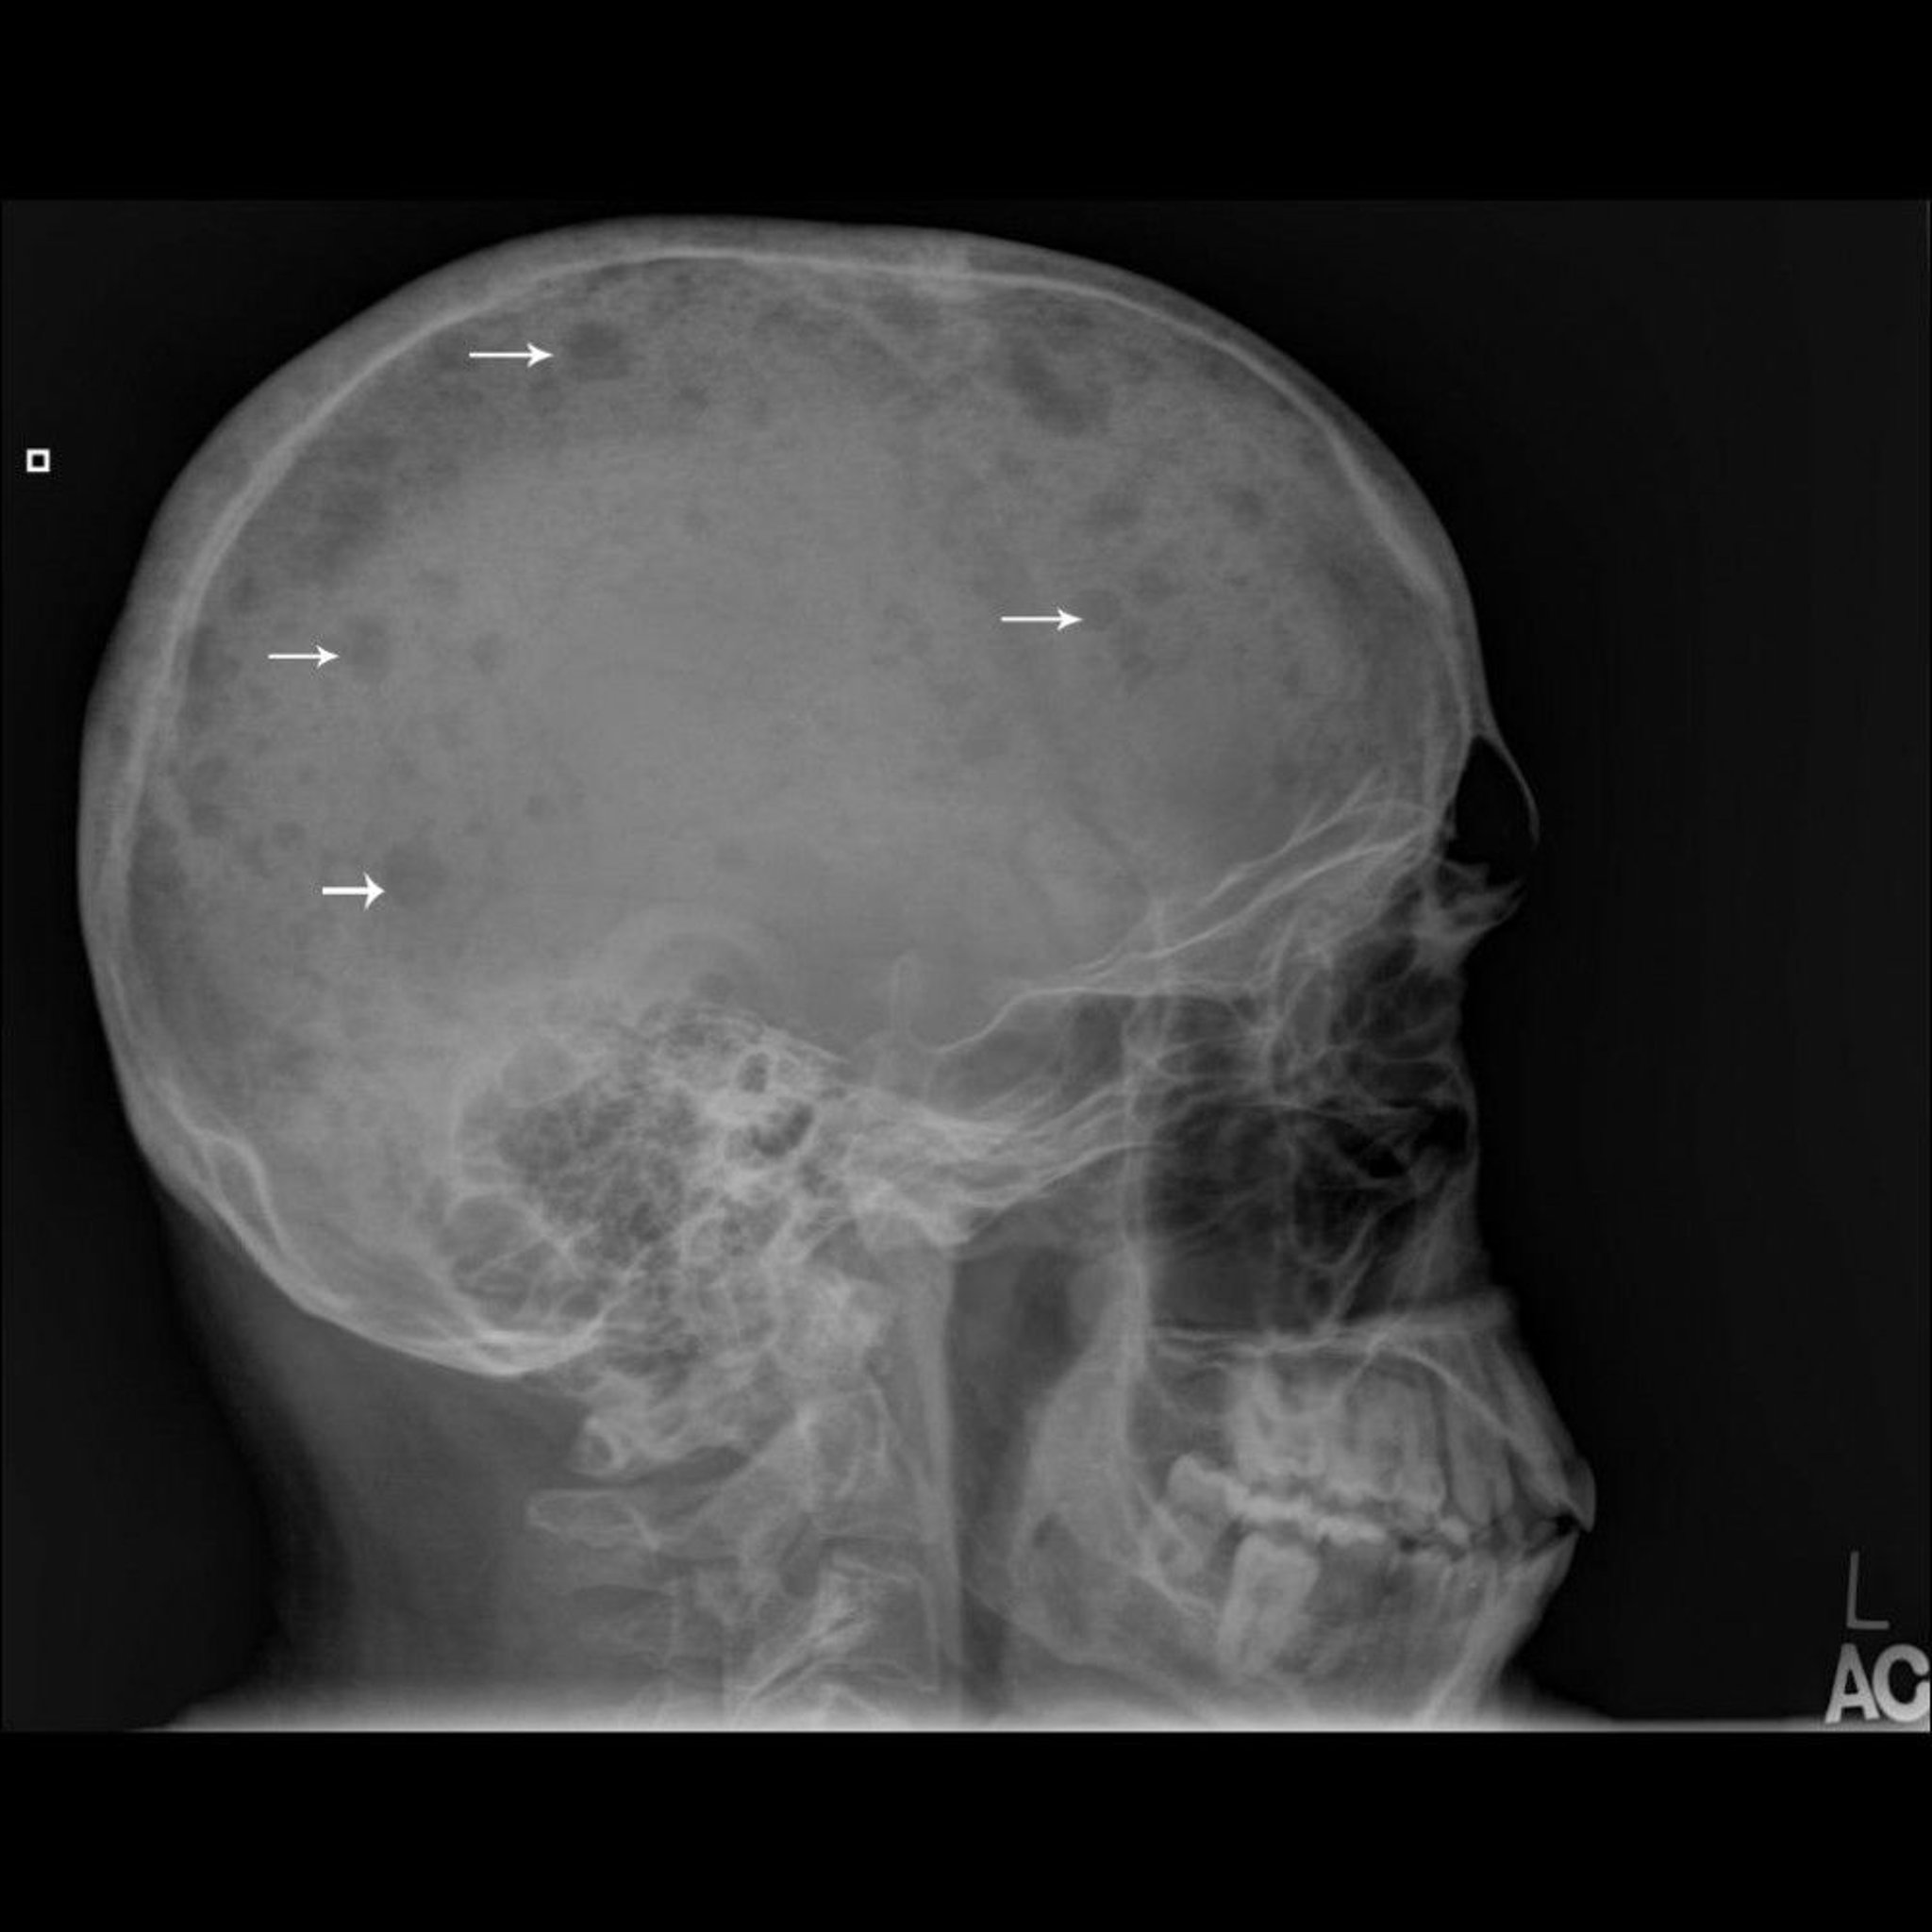

Esta radiografía de cráneo muestra múltiples lesiones perforadas en el hueso (flechas), que son típicas del mieloma múltiple.

Image courtesy of Michael J. Joyce, MD, and Hakan Ilaslan, MD.